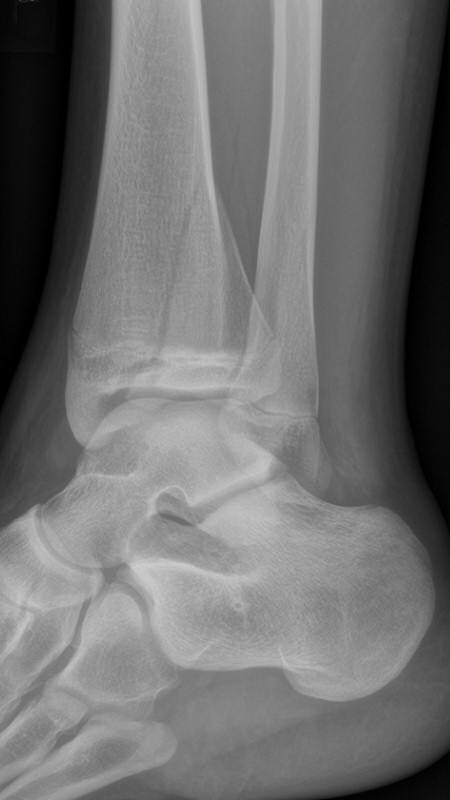

Distal tibiafyseolys SH 4 triplansfraktur (barn)

Triplanfraktur = triplansfraktur = treplansfraktur: fraktur i distala tibia som engagerar både metafys, fys och epifys. Kan vara 2, 3 eller 4 fragment. I 50 % av fallen är även fibula frakturerad [3].

Exempel på triplansfraktur hos nästan färdigvuxet barn

På akutmottagning

Gör DT för att avgöra frakturtyp och felställning.